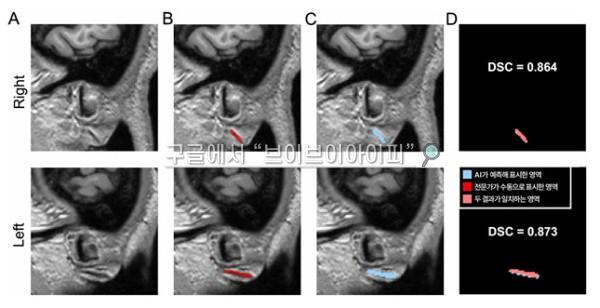

검증 과정에서는 전문가가 수동 표시한 프랭크 징후 영역과 AI가 자동으로 분할한 영역을 비교해 AI의 정확도를 평가했다. 여기서 ‘분할(segmentation)’이란 색칠 공부할 때 특정 부분만 색을 칠하듯이, AI가 귓불 주름을 찾아 표시하는 작업을 의미한다.

그 결과, 전문가가 수동으로 표시한 영역과 AI가 자동으로 분할한 영역의 일치 정도를 측정하는 DSC(Dice 유사도 계수, 1에 가까울수록 유사) 값이 두 차례의 검증에서 0.734, 0.714로 나타났다. 이는 AI가 찾아낸 영역이 전문가의 판단과 70% 이상 부합한다는 뜻으로, 의료영상 분야에서 높은 수준으로 인정받는다.